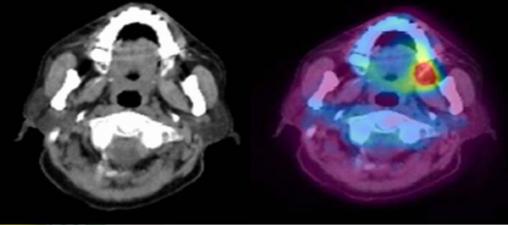

Coupes axiales d’un TEP TDM A gauche, le scanner (TDM) permet une analyse fine des structures anatomiques. A droite, la scintigraphie au fluor marqué (TEP) permet de révéler la présence d’un foyer hyper-métabolique suspect d’une origine tumorale maligne.